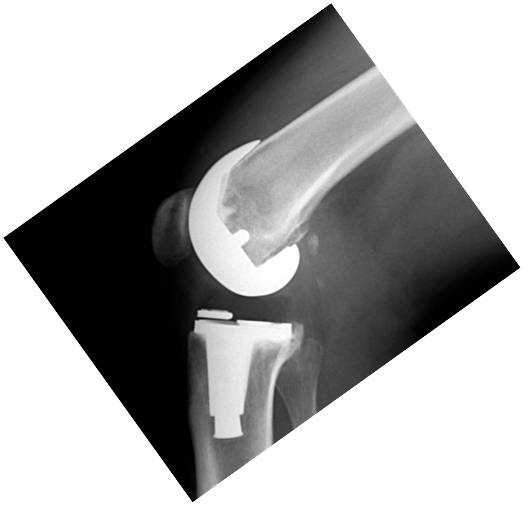

Introducción: El objetivo de este trabajo fue analizar los resultados funcionales y el rango de movimiento entre tres grupos de pacientes con artroplastia total de rodilla: dos utilizando prótesis de alta flexión y el otro con un diseño convencional. Materiales y Métodos: 64 pacientes fueron operados con prótesis total de rodilla Zimmer NexGen®, y 34 pacientes operados con Optetrack ® de alta flexión. Luego de la exclusión de pacientes; 22 pacientes (grupo A) fueron tratados con diseño de alta flexión de Zimmer, 21 pacientes (grupo B) tratados con prótesis Zimmer convencional, y 25 pacientes (Grupo C) con artroplastia Optetrack® PS. La evaluación funcional se realizó con el Knee Society Score, el Western Ontario and McMaster Universities osteoathritis index y la escala analógica visual. Resultados: En el posoperatorio, el promedio de flexión máxima del grupo A subió de 99° a 113º, con un aumento promedio de 14º, en el grupo B de 106° a 118º con una ganancia promedio de 12º y en el grupo C de 110° a 111° siendo la ganancia de 1°. Los resultados funcionales evaluados con KSS y el WOMAC presentaron mejorías en los tres grupos. Conclusión: Las evaluaciones clínicas funcionales son favorables en los tres diseños evaluados. Este estudio muestra que no hay diferencias significativas en la flexión final lograda, y resultados funcionales entre los dos primeros diseños entre sí, si siendo estos significativamente superiores al diseño del tercer grupo luego de un año de seguimiento. Palabras Claves: Prótesis total de rodilla, prótesis de alta flexión, prótesis convencionales, rango de movilidadDescargas